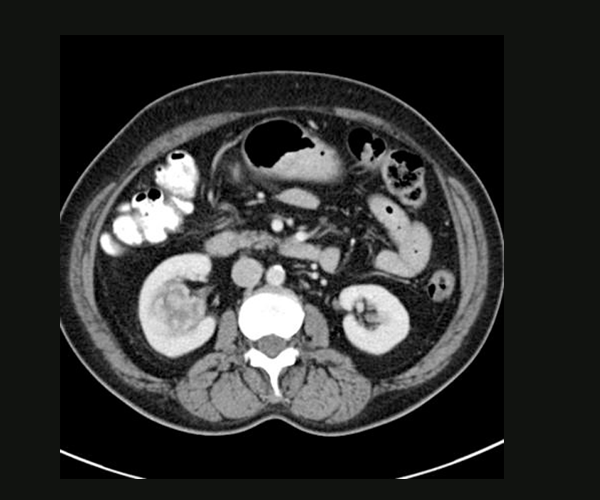

CT IMAGE SHOWING RIGHT RENAL PELVIC

KIDNEY CANCER

Renal cell carcinoma is the most common type of kidney cancer in adults, which accounts for about 90 percent of malignant tumors of the kidney & is the most lethal of the common urologic cancers. This begins in the cells of kidney. Other less common types of kidney cancer can occur. Young children are more likely to develop a particular type of kidney cancer called Wilms' tumor. Because of the location of the kidney within the retroperitoneum, many kidney masses remain asymptomatic and non-palpable until they are locally advanced. The incidence of kidney cancer seems to be increasing. With the more prevalent use of non-invasive imaging techniques such as computerized tomography (CT) scans for the evaluation of a variety of nonspecific symptoms, more than 60% of kidney cancers are now detected incidentally. In many cases, kidney cancer is found at an early stage, when the tumors are small and confined to the kidney, making them easier to treat.

TUMOR AT LOWER POLE OF RIGHT KIDNEY